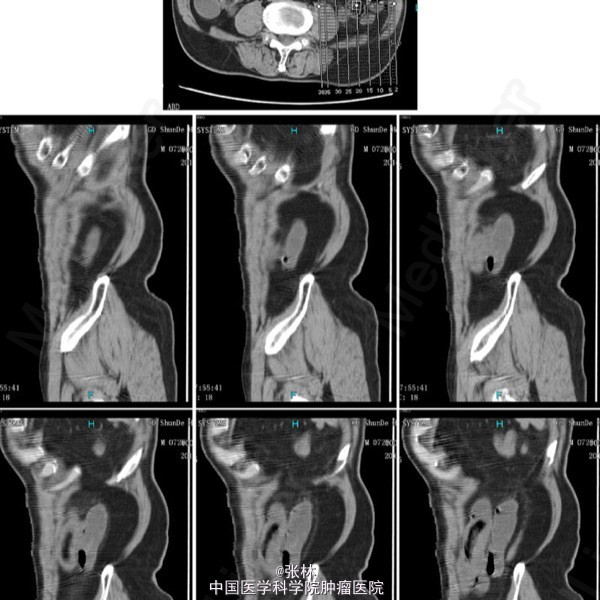

男性,72岁。 主诉:突发腹痛、腹胀伴呕吐1天。 现病史:患者1天前无诱因感全腹部疼痛,呈阵发性绞痛,无放射痛,疼痛开始不剧,伴有畏寒,呕吐胃内容物1次,量约30ml。遂到我院门诊就诊,考虑为急性胃肠炎,予抗炎、解痉护胃等支持治疗,症状未见好转,并进行性加重而入住我科。 专科检查:全腹稍胀,未见肠型及蠕动波,无上腹搏动。腹软,中下轻压痛,无反跳痛。全腹未及肿块,肠鸣音活跃,7次/分。 术中所见:探查见异物位于回肠距回盲部约50cm,大小约8*3*2cm,堵塞肠管,近端肠管充血水肿明显,肠管扩张最大处直径约8cm,未见浆膜层破裂损伤等,系膜无扭转,有少许渗液,探查全部小肠未及肿物腹腔内可见中等量黄色积液,稍浑浊,网膜及腹膜有少量脓苔。洗净腹腔内积液,于肿物边缘对肠系膜缘纵行切开约2cm,取出异物,为半个大小约8*3*2cm的冬菇。